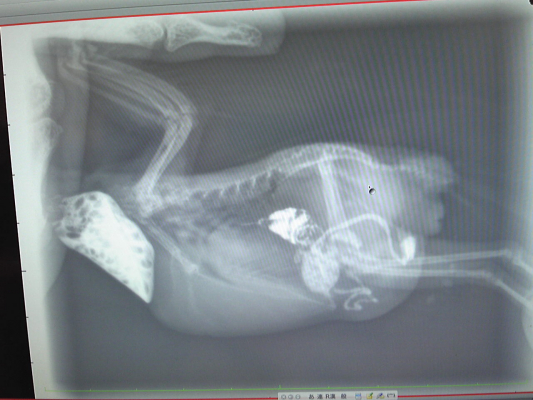

では、現在のココ様のスッキリしたお腹の写真と、

卵巣が腫れてた時のレントゲン写真をご覧下さい。